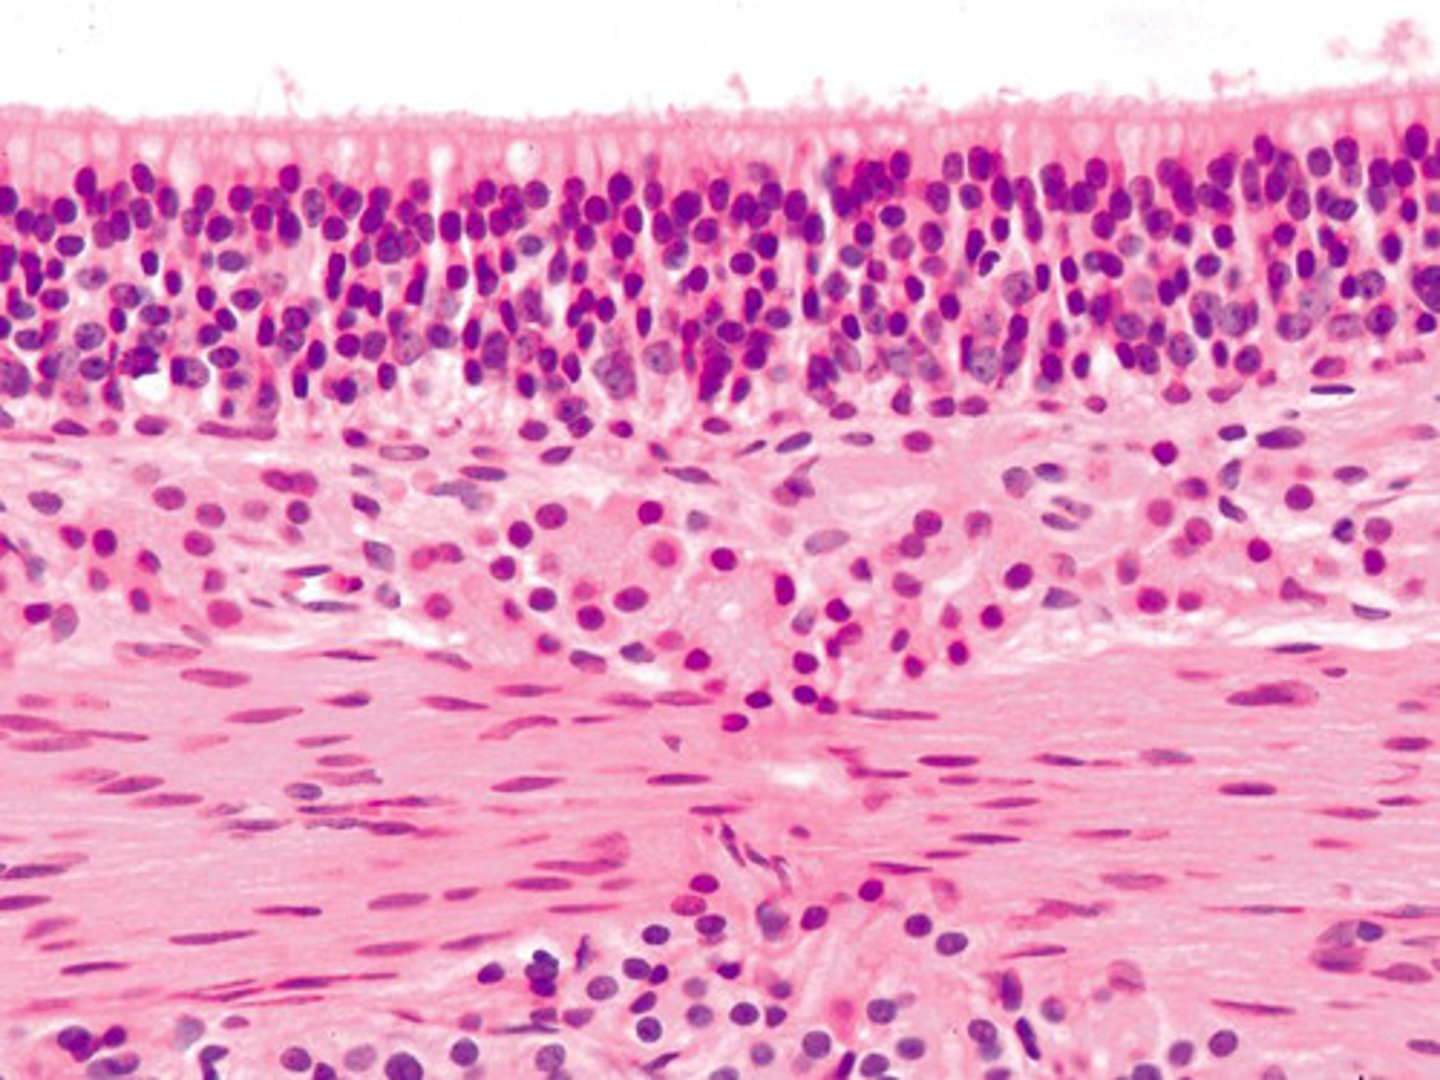

lung histology

alveolar type 1 cell

flat, gas exchange

alveolar type 2 cell

cuboidal, secrete surfactant

capillary endothelium histology

squamous cell on the capillary in alveolus